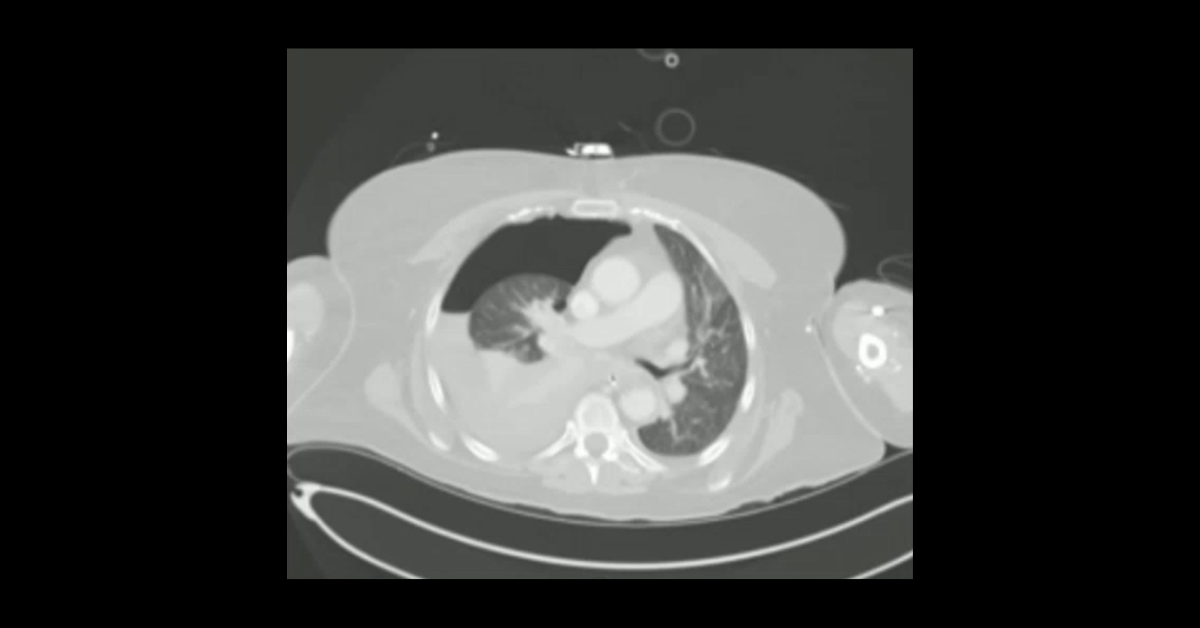

Presented by Vincent Mellnick, MD at Practical Radiology 2025. The upper gastrointestinal tract can be oft-overlooked site of disease in the emergency department patient, but is frequently be the site of pathology, including inflammation/infection, ischemia, obstruction, perforation, and hemorrhage. This talk will discuss common (and some uncommon) conditions causing these presentations in the esophagus, stomach, and duodenum, with emphasis on CT findings.